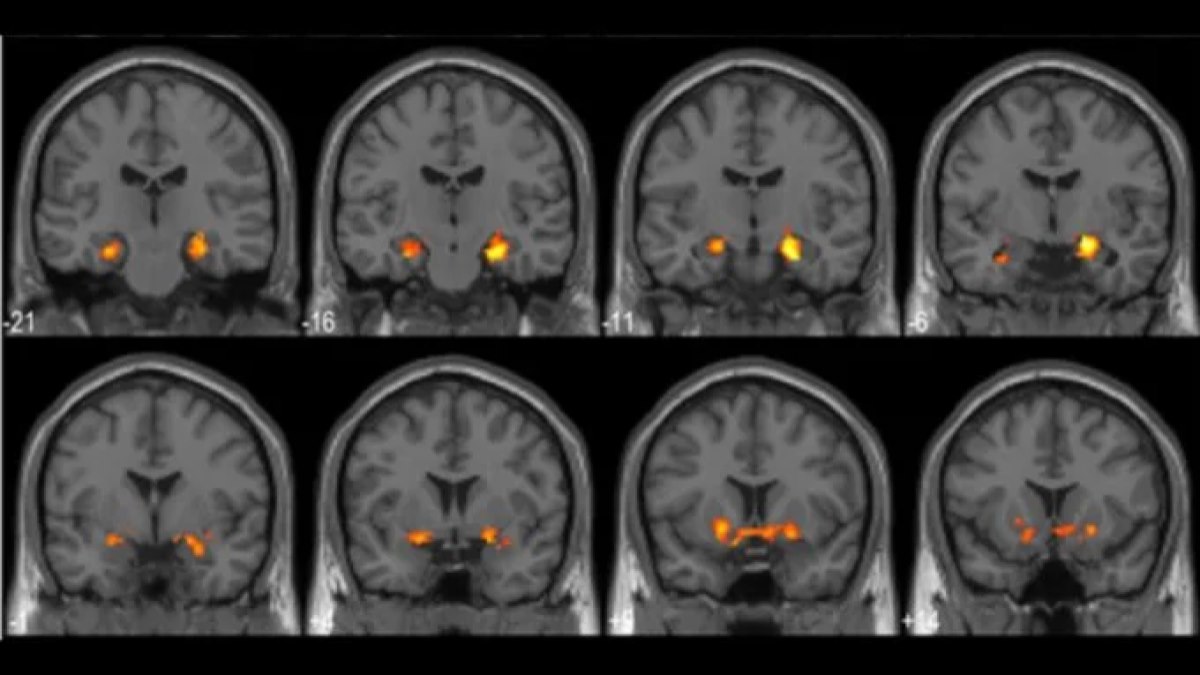

همزمان با حل معماها، فعالیت مغزی شرکتکنندگان با استفاده از دستگاه تصویربرداری fMRI ثبت شد؛ ابزاری که با اندازهگیری جریان خون، سطح فعالیت مغز را نشان میدهد.

تصویربرداریها نشان داد که این لحظات کشف باعث افزایش چشمگیر فعالیت در ناحیه هیپوکامپ مغز میشوند؛ بخشی که نقش کلیدی در یادگیری و حافظه دارد. همچنین الگوی فعالیت نورونها در ناحیه قشر بینایی (مخصوص شناسایی الگوهای تصویری) تغییر میکرد. هرچه لحظه کشف قویتر بود، این تغییرات نیز پررنگتر بودند.

ماکسی بکر، عصبشناس شناختی از دانشگاه Humboldt و نویسنده اول این مقاله، میگوید که در این لحظات مغز بهگونهای متفاوت به تصویر نگاه میکند. به گفته او، وقتی کشف رخ میدهد، بخشهای مختلف مغز ارتباط مؤثرتری با یکدیگر برقرار میکنند.